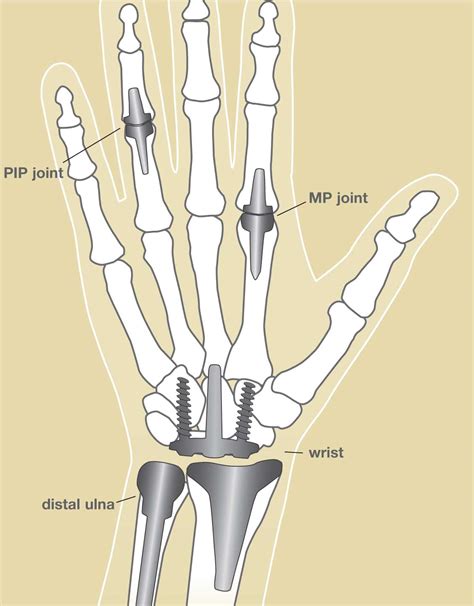

The thumb is a crucial part of the hand, enabling us to grasp, pinch, and manipulate objects with precision. It consists of several joints that work together to provide a wide range of motion. The primary joints in the thumb are:

• Metacarpophalangeal (MCP) Joint: This is the joint at the base of the thumb where the thumb meets the hand.

• Interphalangeal (IP) Joint: This is the joint near the tip of the thumb.

• Carpometacarpal (CMC) Joint: This is the joint at the base of the thumb where it connects to the wrist.

Each of these joints plays a vital role in the thumb's functionality, and issues with any of them can lead to pain and reduced mobility.

• Joint Fusion: Fusing the bones in the joint to eliminate pain and improve stability.

• Joint Replacement: Replacing the damaged joint with an artificial implant.